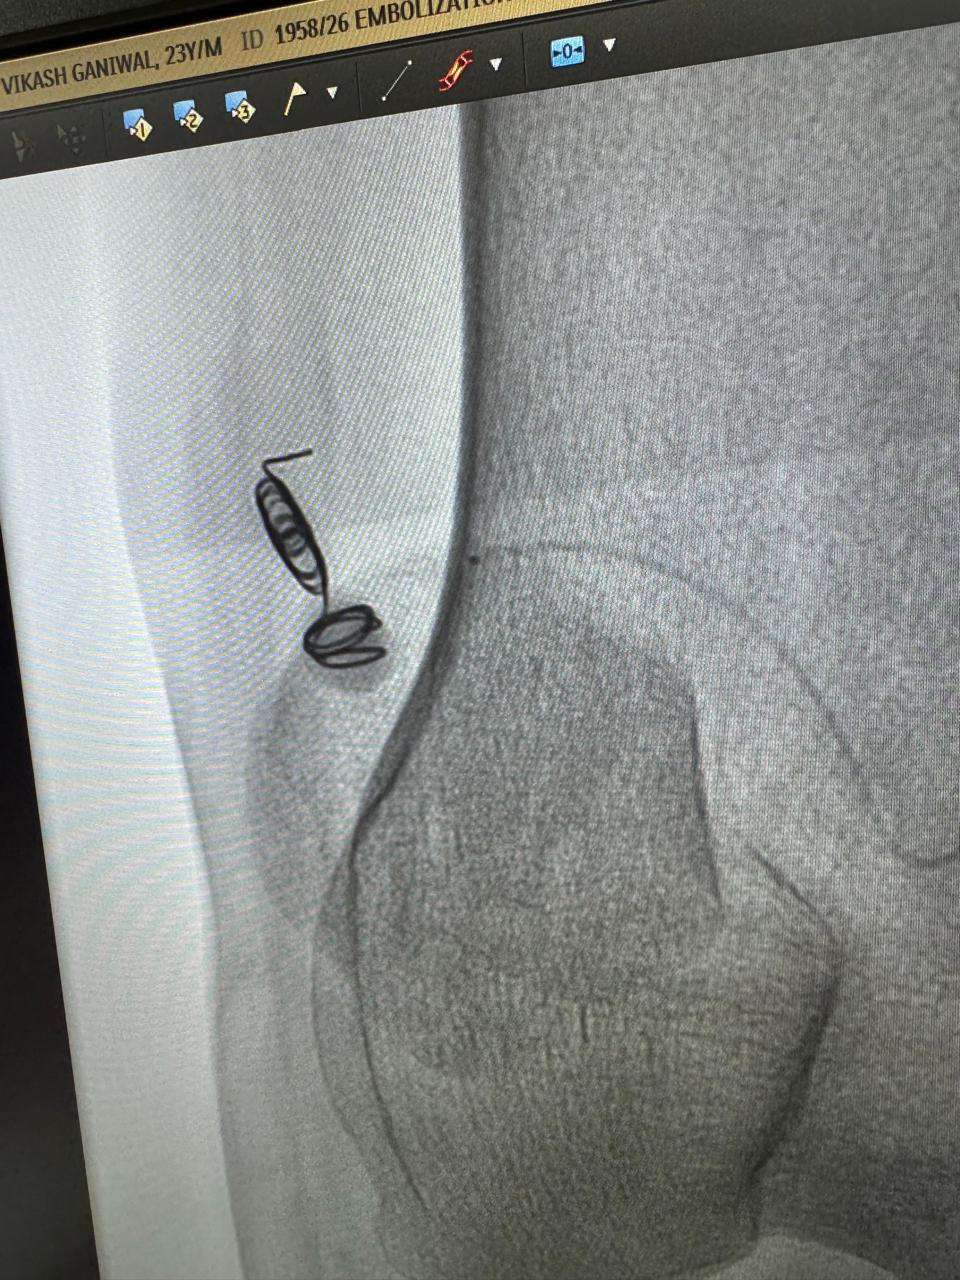

Pseudoanurysm Of Radiocephalic Fistula